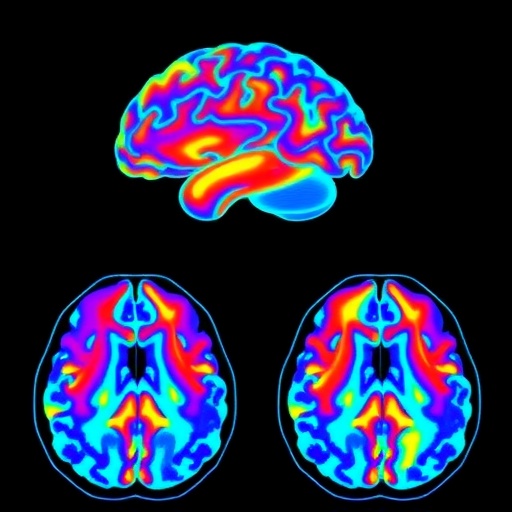

In a groundbreaking study, researchers have introduced an innovative framework known as Mod-SE(2), which utilizes geometric deep learning techniques to tackle the formidable challenges posed by brain tumor classification and segmentation in magnetic resonance imaging (MRI) scans. This significant advancement stands as a beacon of hope for medical professionals who rely on precise diagnostic tools for effective treatment planning and patient prognosis.

This novel approach centers on leveraging the intrinsic geometric properties of images to improve the classification and segmentation processes. Traditional convolutional neural networks (CNNs) have transformed medical image analysis, but they often struggle with the complex shapes and variances found in anatomical structures. By incorporating a geometric perspective, Mod-SE(2) enhances the model’s ability to understand and process the manifold that is represented by brain complexities, offering a contrast to the linear interpretations of classical methods.

The heart of Mod-SE(2) lies in its unique architecture that harmonizes spatial and spectral information. By treating the MRI data in a way that respects its geometric nature, this framework can more effectively interpret the varying shapes of brain tumors, which is crucial for both accurate diagnosis and targeted treatment planning. The model’s ability to perceive the image data in this multidimensional framework marks a substantial leap forward in medical imaging technologies.